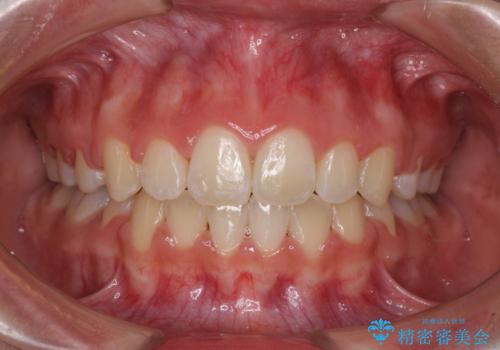

オープンバイトをインビザラインで矯正治療

非抜歯、ワイヤーでの矯正治療。歯のがたつき、顎のズレ、出っ歯を治す。インビザラインが使えない方